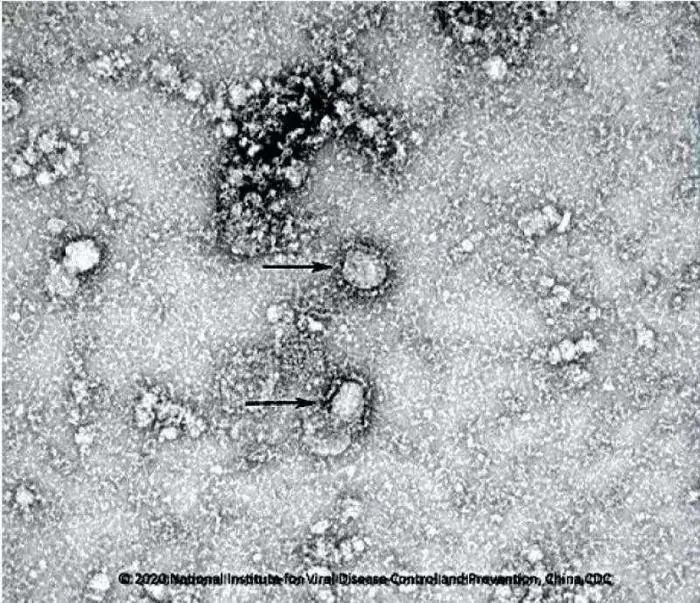

1月24日,新型冠状病毒国家科技资源服务系统正式启动,上午9时20分,服务系统首次向全球发出新冠病毒的电镜照片及毒株信息,3小时后,美国有线电视新闻网(CNN)等国际媒体对此进行了报道。

国家病原微生物资源库公布首株新型冠状病毒毒种信息。图片来源:中国疾控中心网站